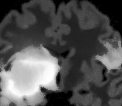

V-C Non-Registered MRI Segmentation Experiments

To demonstrate the robustness of the superpatch structure and the proposed framework, we apply SPM to brain tumor segmentation on multi-modal non-registered Magnetic Resonance Images (MRI). Classical patch-based and multi-atlas structure segmentation methods are based on registered subjects. Consequently, they cannot be efficiently applied in this non-registered context, due to the substantial variation in tumor shape and locations. Superpixels enable to better capture the tumor geometry, thus increasing the segmentation accuracy. Superpixel and supervoxel-based approaches have been applied to tumor segmentation [54]. However, in this work, the neighborhood is not considered and the ANN search is exhaustive, and computed on a large multi-modal histogram descriptor, leading to prohibitive computational time.

SPM can be efficiently applied to tumor segmentation since it quickly finds good correspondences without image registration, and uses the superpixel neighborhood to improve the matching. In this application, the segmentation is computed from a superpixel decomposition [1], then each region (tumor or background) is labeled with SPM.

We present results obtained on the MICCAI multi-modal Brain Tumor Segmentation (BRATS) dataset [49]. This challenging dataset contains real and simulated patient data, with overall poor resolution and large variation of tumor shape and position. For both types, high grade (HG) and low grade (LG) tumors are provided with four modalities: T1, contrast enhanced T1 (T1C), T2, and FLAIR. Overall, there are 20 and 10 real patient data with respectively HG and LG tumors, and 25 images for both HG and LG simulated tumor data. We use the same SPM parameters as in Section V-B, taking a multi-modal histogram, containing the levels of gray intensity on all MRI modalities as descriptor for superpatch matching, and performing the regularization (8) at the pixel scale to compare with pixel-wise ground truths. Each subject is segmented by the remaining of its type in a leave-one-out procedure.

In Fig. 12, we show several tumor segmentation results for all data types.

In Table II, we compare results obtained using different descriptor structures:

patch-based [48], superpixel-based [54],

and superpatch-based (= pixels).

We use the Dice coefficient [55] as evaluation metric,

measuring the overlap between the automatically segmented structure and the ground truth.

The superpixel-based approach

appears very limited since it fails at capturing the tumor context and their location in other images.

Regular patches are also limited in this context, due to the variations in the structure shapes.

Superpatches provide a robust descriptor, since they follow image intensities and capture the superpixel neighborhood,

leading to more accurate segmentation.

These experiments demonstrate that superpatches within the SPM framework provide fast and accurate segmentation results

even on non-registered multi-modal images with poor resolution.